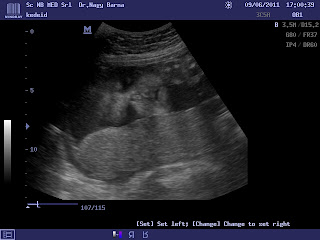

Greti megtekintese!

Ma voltunk UH-n , nagyon jo volt vegre ujra latni , mar 7 hete nem lattuk, nagyon edi baba volt asitott nagyokat, irto faradt volt a dragam:) viccelek, de biztos belefaradt amig engem rugdosott egesz nap, hisz egy orokmozgo kiscsaj. Krisz addig nagyinal volt , jatszottak, ugyes fiu volt . Greti mar 1100 g-ot nyom, a doki szerint nagyobb is vagyis sulyosabb is a korahoz kepest es nagyon elvezi odabent magat. megmutatta ujbol a nunijat nem szegyelte magat , lattam a kis taplacskait is. es neki is olyan pise ora van mind nekem.

Rakok egy par kepet a dragaimrol.